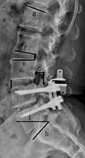

(1)临床评估:在术前和术后随访点进行腰痛、腿痛VAS评分及ODI评分。计算ODI改善率=(术前ODI评分-术后ODI评分)/术前ODI评分×100%。>50%临床疗效优,25%~50%为疗效好,<25%无改变或差。VAS降低20为显著改善。(2)影像学评估:术前和随访点行腰椎正侧位、过屈过伸位X线片,使用Surgimap Spine软件(Nemaris Inc,美国)测量腰椎前凸角(lumbar lordosis,LL)和骶骨倾斜角(sacral slope,SS)、Coflex节段和邻近节段[椎间隙高度、椎间活动度(ROM)、椎间孔高度和宽度];术前MRI对椎间盘Pfirrmann分级和终板Modic分级,CT对关节突关节增生分级(图1)。(3)ASD诊断标准:以下任何1项均可:①椎间盘高度丢失≥50%[13];②椎体滑移≥4 mm[13];③ROM>10°[14]。其中椎体滑移≥4 mm为早发性ASD。